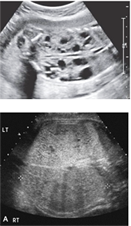

- : UTD는 kidney의 antero-posterior renal pelvic diameter (APRPD)를 측정해야 하며, 정상 범위는 28주 미만에서 4 mm 미만, 28주 이상에서는 7 mm 미만이어야 합니다. 다음 그림과 같이 fetal spine을 probe에 가깝게 두고 양측 kidneys의 APRPD를 측정하는 것이 가장 올바른 방법입니다.